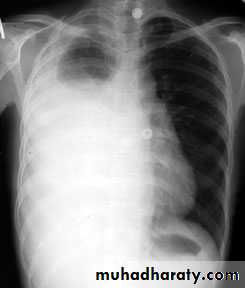

Massive pleural effusion